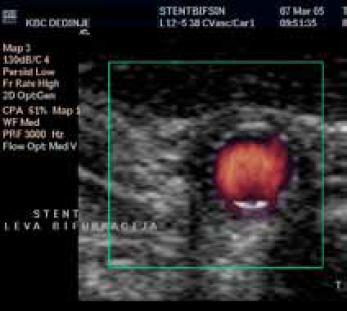

Karotidna restenoza na samoj bifurkaciji, glatke površine (A), Restenoza je rešena plasiranjem stenta.

Implantacija stenta u bifurkaciju zbog karotidne restenoze – Power Doppler uredan kontrolni follow up nalaz. Nema restenoze

Implantacija stenta u bifurkaciju

zbog karotidne restenoze.

Uredan kontrolni follow up nalaz.

Nema restenoze

Color Duplex ultrasonografija

B mod ultrazvuk